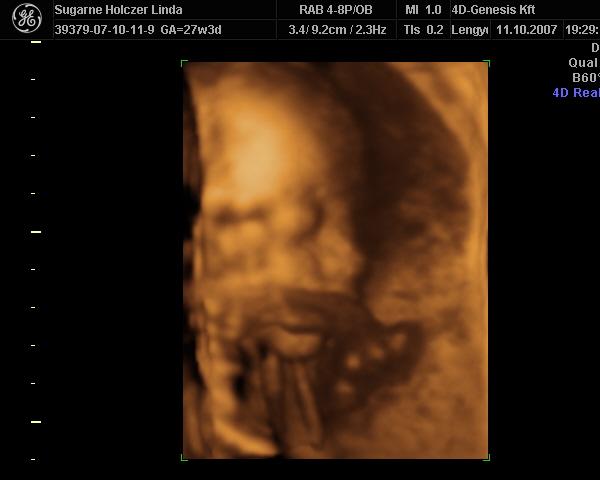

Ind, gyönyörű babád van

– köszi a képeket

Azt még megkérdezem, hogy ti most tulajdonképpen mennyi idősök vagytok? – a kép szerint 27hét+3nap, a vonalzód szerint pedig 26 hét.... – nagyobb a babád, mint kellene?